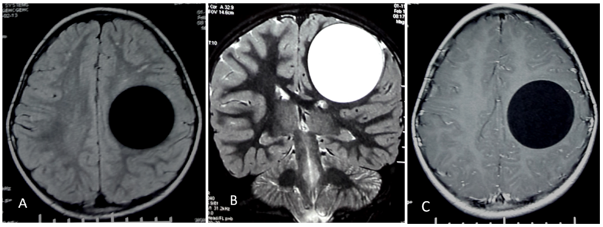

A 16 year old male from a rural area was admitted to our neurosurgery department with complaints of headache and vomiting. Physical exam noted a right hemiparesis. MRI demonstrated a cystic mass in the left parietal region measuring 6cm in diameter, with lateral ventricle compression. No peripheral oedema was noted around the cyst. The lesion was with low signal intensity on T1 and high signal on T2 Weighted images and the cystic wall was hyposignal T2. On diffusion weighted images the cyst was like cerebrospinal fluid. No enhancement was seen (Figure 1).

Figure 1: Cerebral MRI: FLAIR axial (A), T2 coronal (B) and T1 with contrast (C) images showing fronto parietal cyst compressing the frontal horn. The cyst is like cerebrospinal fluid and the cystic wall is hypo signal T2 suggestive of Hydatid cyst.